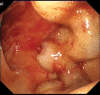

Background: Esophagogastric variceal bleeding (EGVB) is a potentially life-threatening complication of portal hypertension. Endoscopic treatment combined with pharmacotherapy remains the mainstay in the management of acute variceal bleeding.

Results: A total of 85 questionnaires were collected. There was no statistical difference in the selection of items (P < .05 indicated statistical significance). The majority of endoscopists (95.29%) offered EGV screening for patients with liver cirrhosis. The location, diameter, and risk factor classification was selected by 82.35% of endoscopists. Endoscopy + medication was preferred (42.35%) for the primary prophylaxis of moderate-to-severe EGVs. There was no statistical difference in emergency intervention time for active EGVB (P > .05). The response "patients receive emergency endoscopic intervention within 12 hours" was selected by 61.2% of the endoscopists. The preferred emergency treatment for EGVB was combination treatment (40%). Tissue adhesive embolization was selected for the treatment of gastric variceal bleeding by 74.12% of endoscopists; transjugular intrahepatic portosystemic stent shunt/percutaneous transhepatic variceal embolization were selected as remedial measures by 48.23% to 52.94% of endoscopists. In addition, 67.06% of endoscopists elected to perform secondary prophylaxis and treatment within 1 week after hemostasis. Endoscopy and endoscopy + medication were selected by 44.71% and 49.41% of endoscopists, respectively, for secondary prophylaxis. The choice of laboratory indicators did not differ with length of experience.